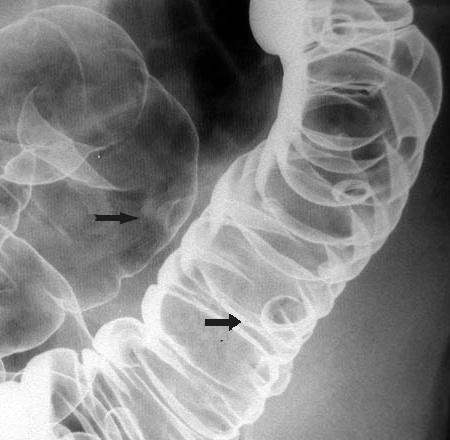

Polyp du colon a sessile

intraluminale . Sa bord lisse et sa pied est tres

large . Lavement bayte en double de contrast |